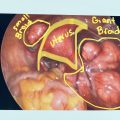

- Laparoscopic myomectomy: Several small incisions are made, and a camera and surgical instruments are inserted to remove the fibroids.